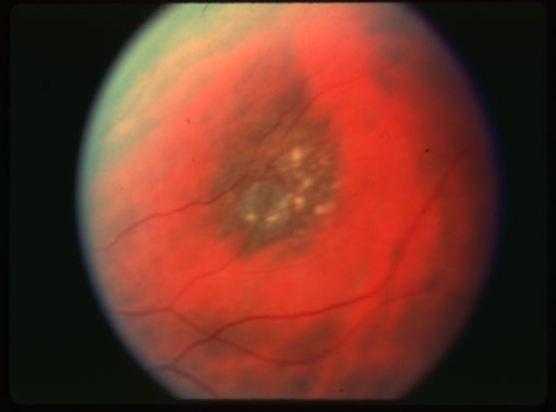

metastatic carcinoma

metastatic carcinoma

metastatic carcinoma

metastatic carcinoma

metastatic carcinoma

metastatic carcinoma

metastatic carcinoma

metastatic carcinoma

metastatic carcinoma

metastatic carcinoma of choroid

more common than primary malignancies

seed of cancer that started in a cancer elsewhere & spread to eye via blood flow

features:

cream, yellow, light brown

flat or slightly elevated mottled pigment clumping on surface

extensive exudative RD

maybe multifocal or bilateral